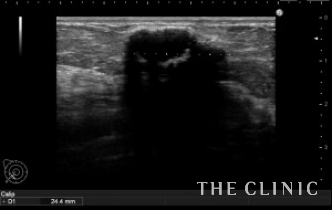

エコー所見です。

左 広範囲に皮膚と癒着しています。